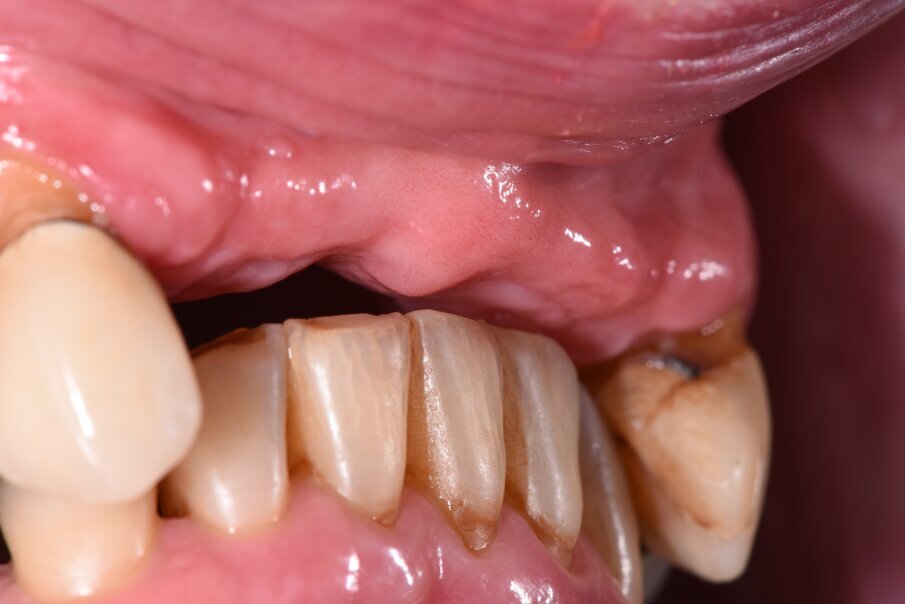

Il caso clinico descrive una situazione complessa di una paziente trattata con radioterapia 5 anni prima per un carcinoma della laringe, in conseguenza del quale era stato rimosso l’intero gruppo incisivo superiore sostituendolo provvisoriamente con una protesi parziale rimovibile stabilizzata con ganci a filo sui canini (Fig. 1). La paziente di 59 aa presentava inoltre delle protesizzazioni fisse nel quadrante I° e III° su elementi naturali, entrambe con vistose infiltrazioni e scheggiature che rendevano i manufatti incongrui. Lo stato parodontale iniziale presentava un sondaggio medio (Tab. 1) spesso associato a mobilità di vario grado e per taluni elementi era presente anche sanguinamento. All’esame obiettivo si evidenzia una complessa situazione clinica riportata di seguito in Tabella 2.

Fig. 1_Foto iniziale con il provvisorio rimovibile in posizione. La presenza di una flangia in resina consente un maggior supporto labiale.

Fig. 2_La mancanza del provvisorio evidenzia parte delle criticità del caso con una dimensione verticale fortemente ridotta.